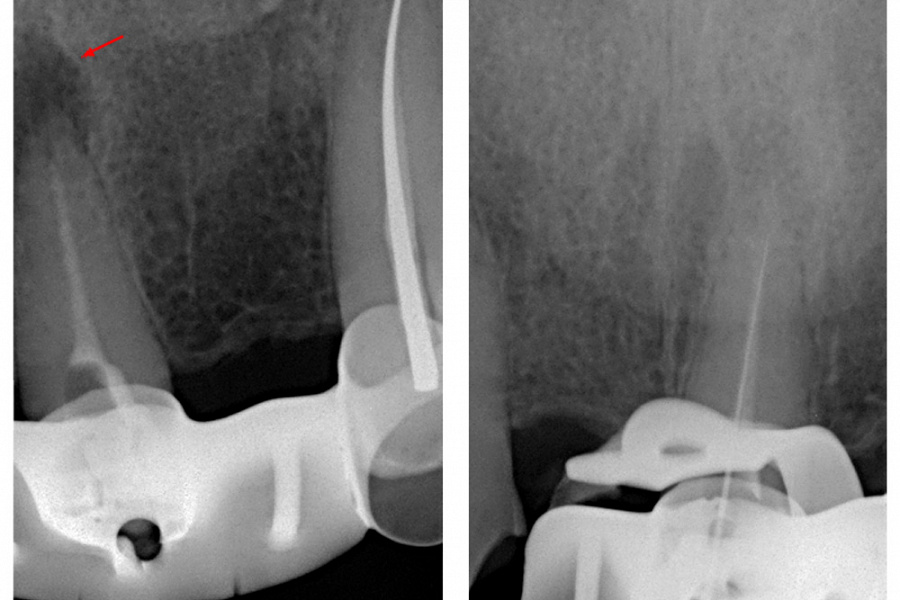

В связи с наличием у пациента жалоб и клинических симптомов принято решение о проведении ревизии корневого канала 21 зуба. Проведена терапия с помощью гидроокиси кальция в течении 4-х недель (снимок 3). Пломбировка канала гуттаперчей и корневым герметиком.